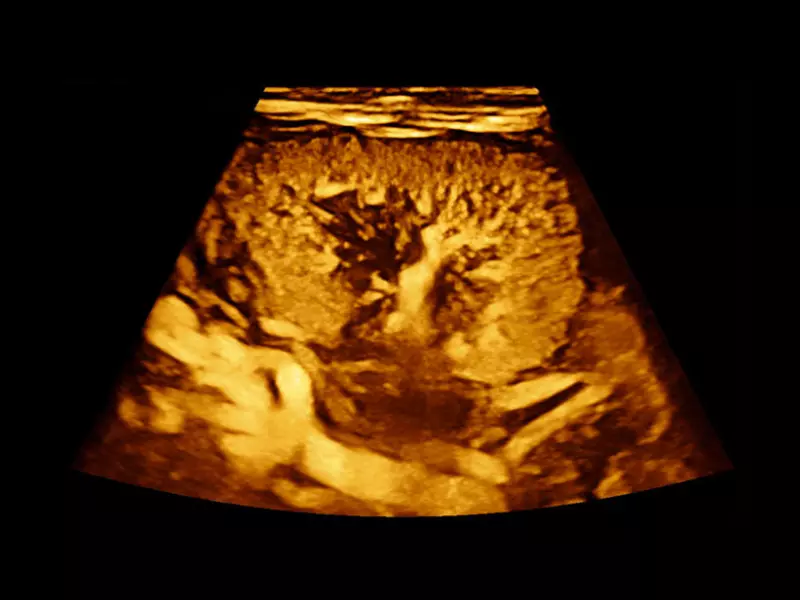

MyLab™9 Platform - XFlow Doppler enhancement in liver vascularization

MyLab™9 Platform - XFlow Doppler enhancement in liver vascularization